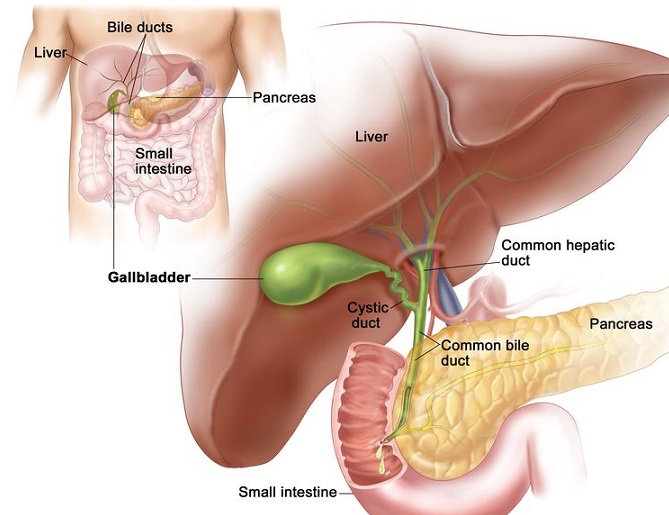

Overview

Package includes:

Days in hospital : 2 to 3 Days (For patient and one attendant)

Days in hotel : 7 Days (For patient and one attendant)

Room type in hospital : Shared

Room type in hotel : Private

Hotel category: Standard

Value added benefits of the Open - Cholecystectomy: